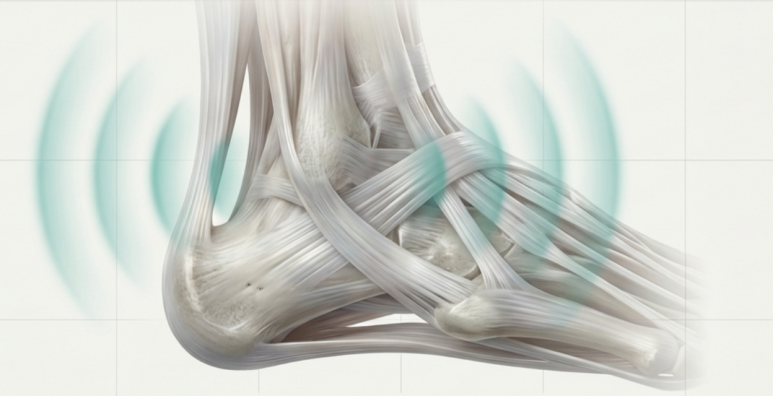

만성 건병증의 핵심적인 병태생리는 염증과 유착, 그리고 힘줄 자체의 변성입니다. 기존 치료법이 한 가지 병리 기전에만 초점을 맞추는 경우가 많아 한계가 있었죠. 이 복합적인 병리 기전을 4단계로 나누어, 초음파를 이용해 병변 부위를 ‘눈으로 보면서’ 단계별로 정확하게 공략하는 것입니다. 한의학의 경혈 초음파의 최대 강점은 문제가 있는 혈자리를 눈으로 보면서 시술하는 ‘정밀 타겟’에 있죠. 그럼 만성 아킬레스건병증의 핵심 병변을 치료하는 4단계 프로토콜을 하나씩 살펴보겠습니다. > 1단계: 주변 염증 잡기 > > 건 주위 조직염 (Paratenonitis)

초음파로 정확하게 확인해서 혈액 공급이 풍부한 골막까지 미세 손상을 유도하면, 주변 혈류가 증가하고 섬유아세포 활동이 활성화되어 콜라겐이 재생됩니다.

이렇게 골막에 자극을 준 상태에서 고주파(100Hz)의 전기를 걸어 조직 재생을 활발하게 촉진하고 진통효과를 극대화시킵니다. > 치료결과 및 예후 해당 환자분은 총 47일 동안 12회 치료를 받았는데요. 치료 전에는 "아침에 첫 발 디딜 때 날카롭게 아프다" 호소하셨고, 통증 평가 점수가 27.8점으로 매우 낮았습니다. 수술 권유까지 받았던 분이죠.